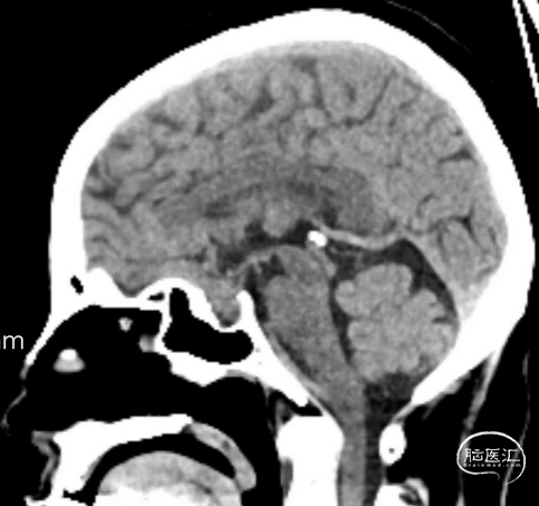

头颅CT:鞍区饱满,蝶鞍等密度占位,未见明显钙化。

头颅增强核磁:蝶鞍可见片条状异常信号影并向前延伸,长度约33mm,高约14mm,垂体显示不清,视交叉受压,增强后强化明显,局部欠均匀,可见脑膜尾征,考虑为脑膜瘤可能。